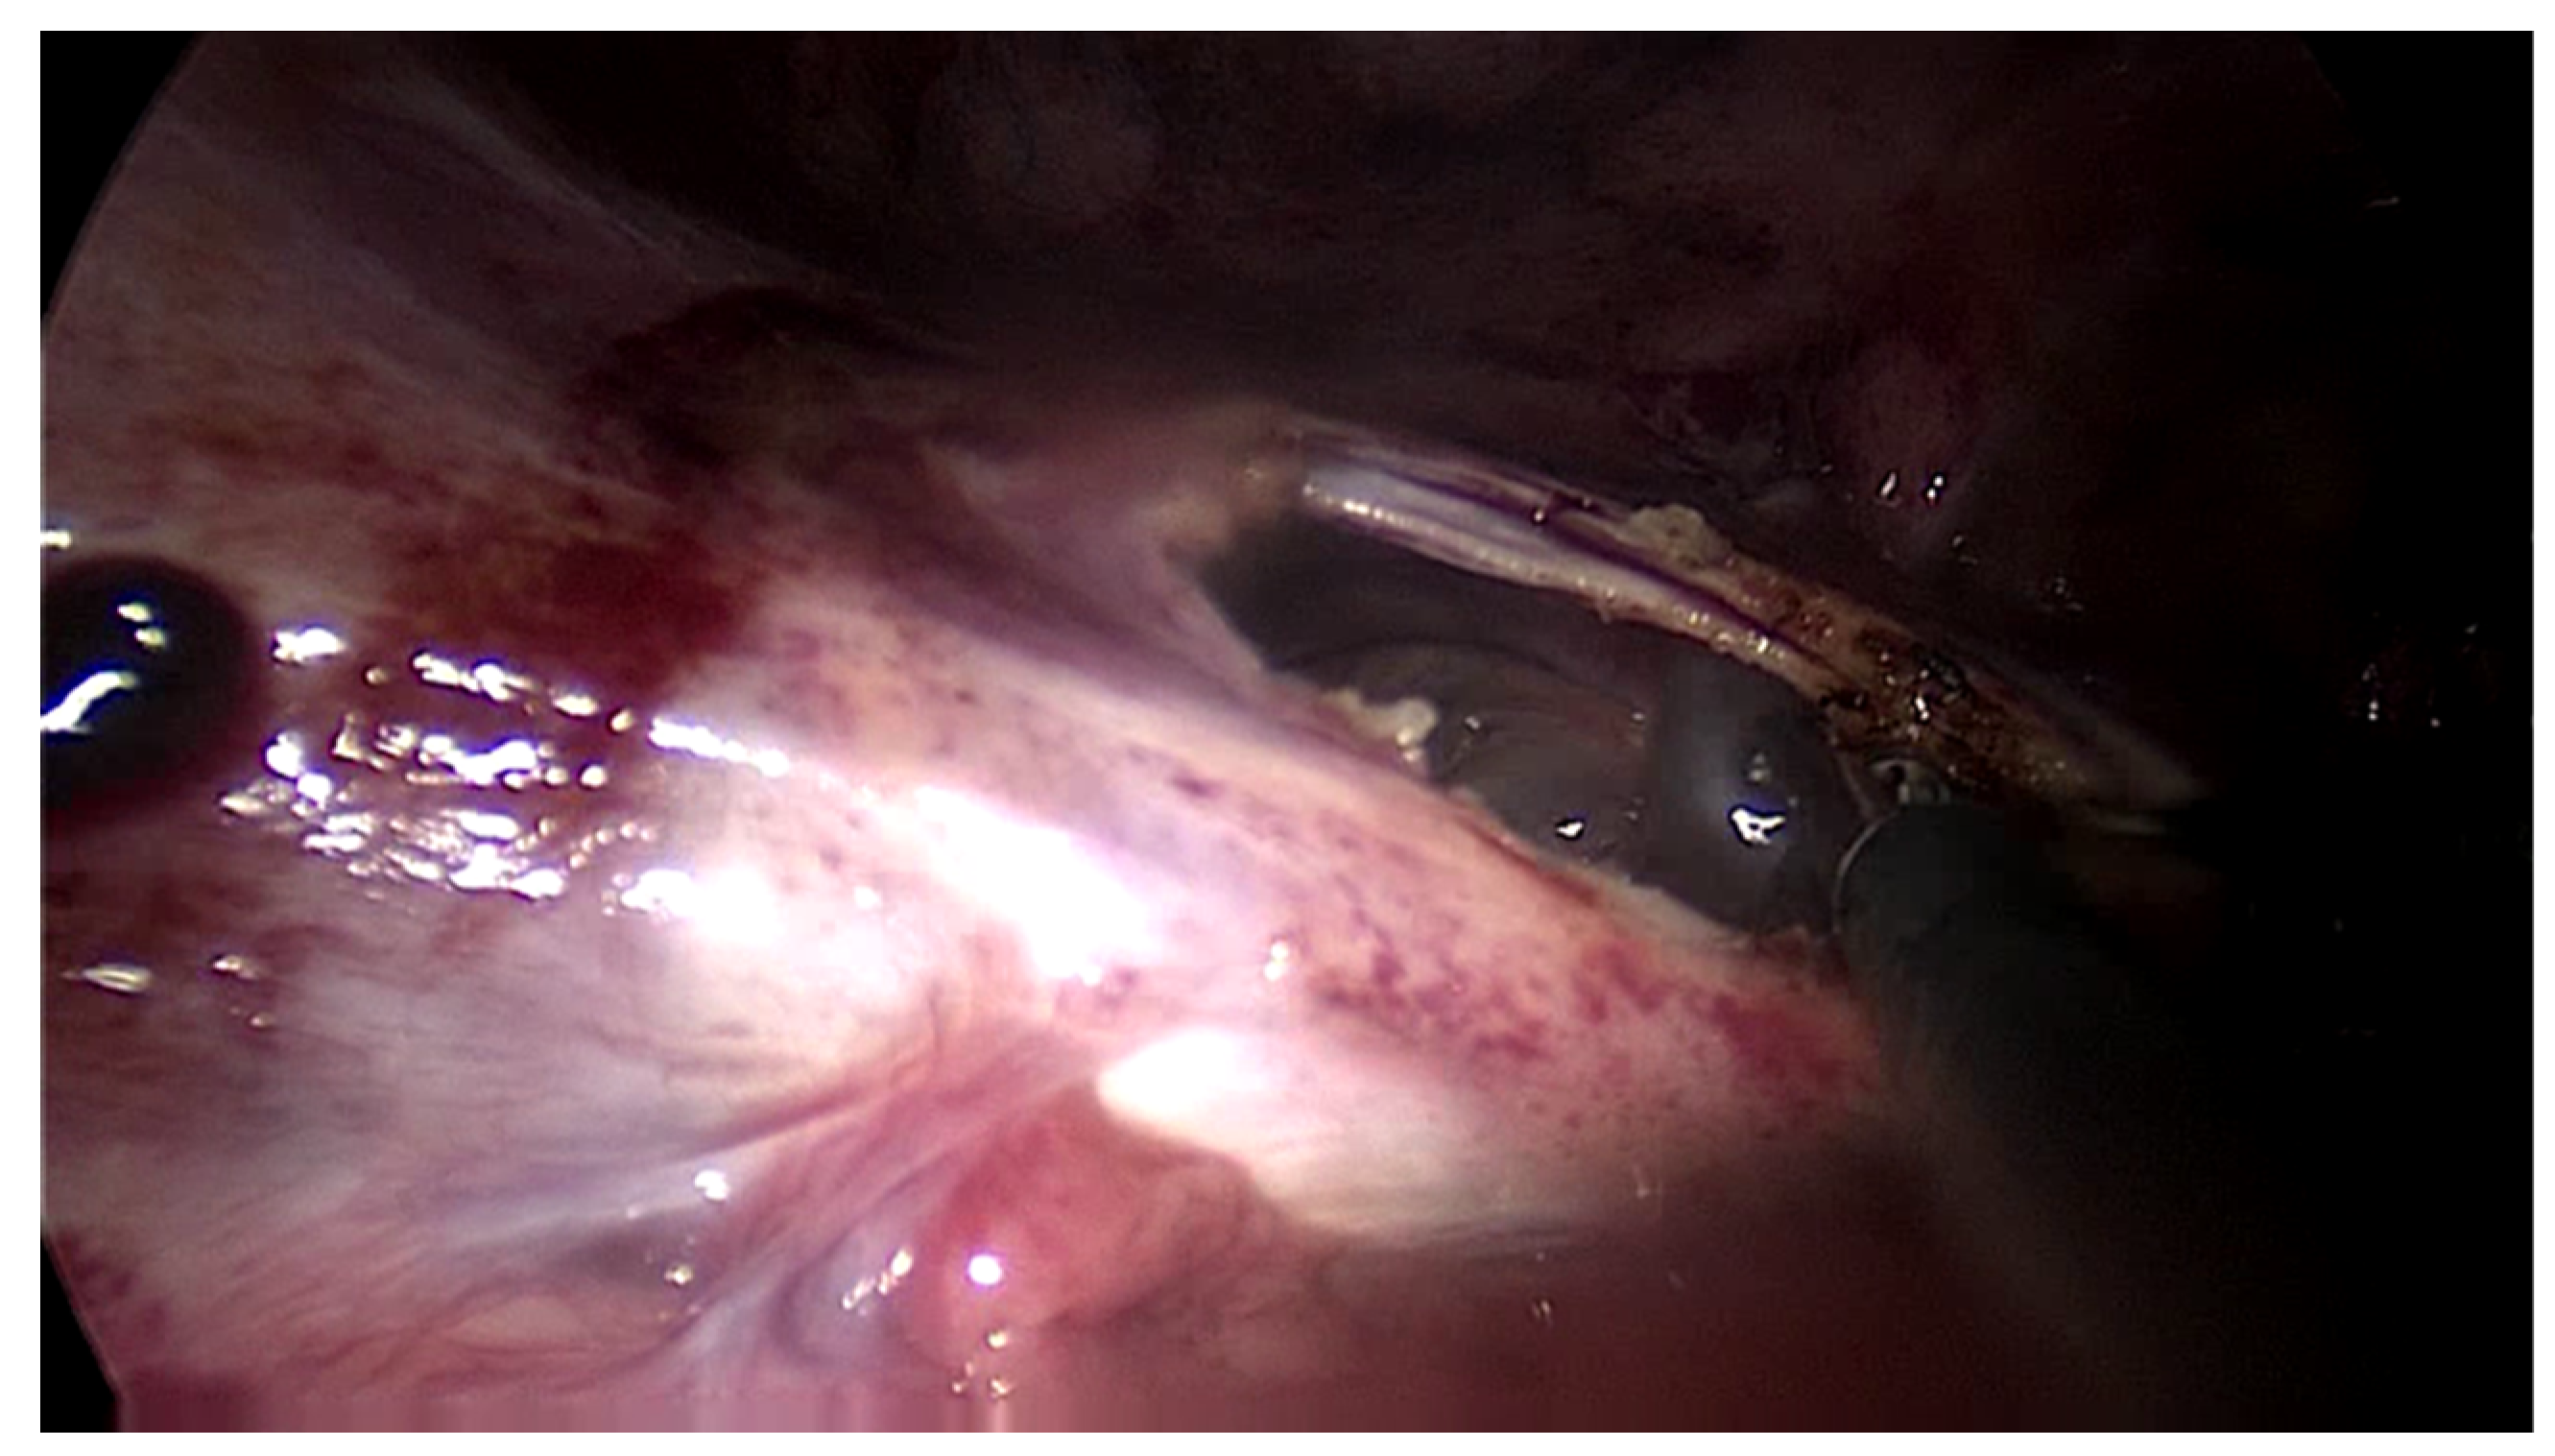

The first patient was a 25-year-old woman with lupus nephritis who had undergone PD for 10 years. The PD history of the patient was associated with three episodes of peritonitis (including Mycobacterium tuberculosis, Enterococcus faecalis and Staphylococcus aureus infections, the last of which was 6 years before presentation) and negative ultrafiltration for several months requiring four hypertonic exchanges daily (2X 1,36% and 2X 3,86% Dianeal PD Solution (Baxter International)) for controlling overhydration. For several months, the patient was suffering from metrorrhagia and bloody effluent for several days. During hospitalization, the effluent became notably hemorrhagic with acute anemia. Emergency surgery was performed revealing hemoperitoneum due to an adnexal pathology. Intraoperatively, we found extensive peritoneal fibrosis encapsulating the small bowel loops and the organs located in the pelvis in a “cocoon” (Image 1). Furthermore, there was significant bleeding from the site where the right adnexa should have been located and the right fallopian tube and right ovary could not be identified. A visceral “block” representing the right adnexa was dissected and isolated with great difficulty, which was resected to stop the source of the intraperitoneal hemorrhage. A final diagnosis of EPS was confirmed by the pathologist. The immediate and late postoperative outcomes were good, without any surgical complications; however, the patient subsequently died 6 months later due to a hemorrhagic stroke.

Image 1. Intraoperative finding – thickened peritoneum.